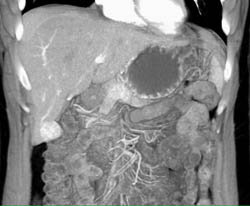

Pseudocyst in Lesser Sac